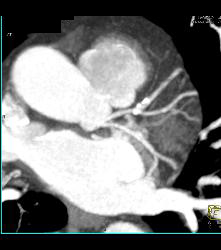

Left Anterior Descending Coronary Artery (LAD) Plaque